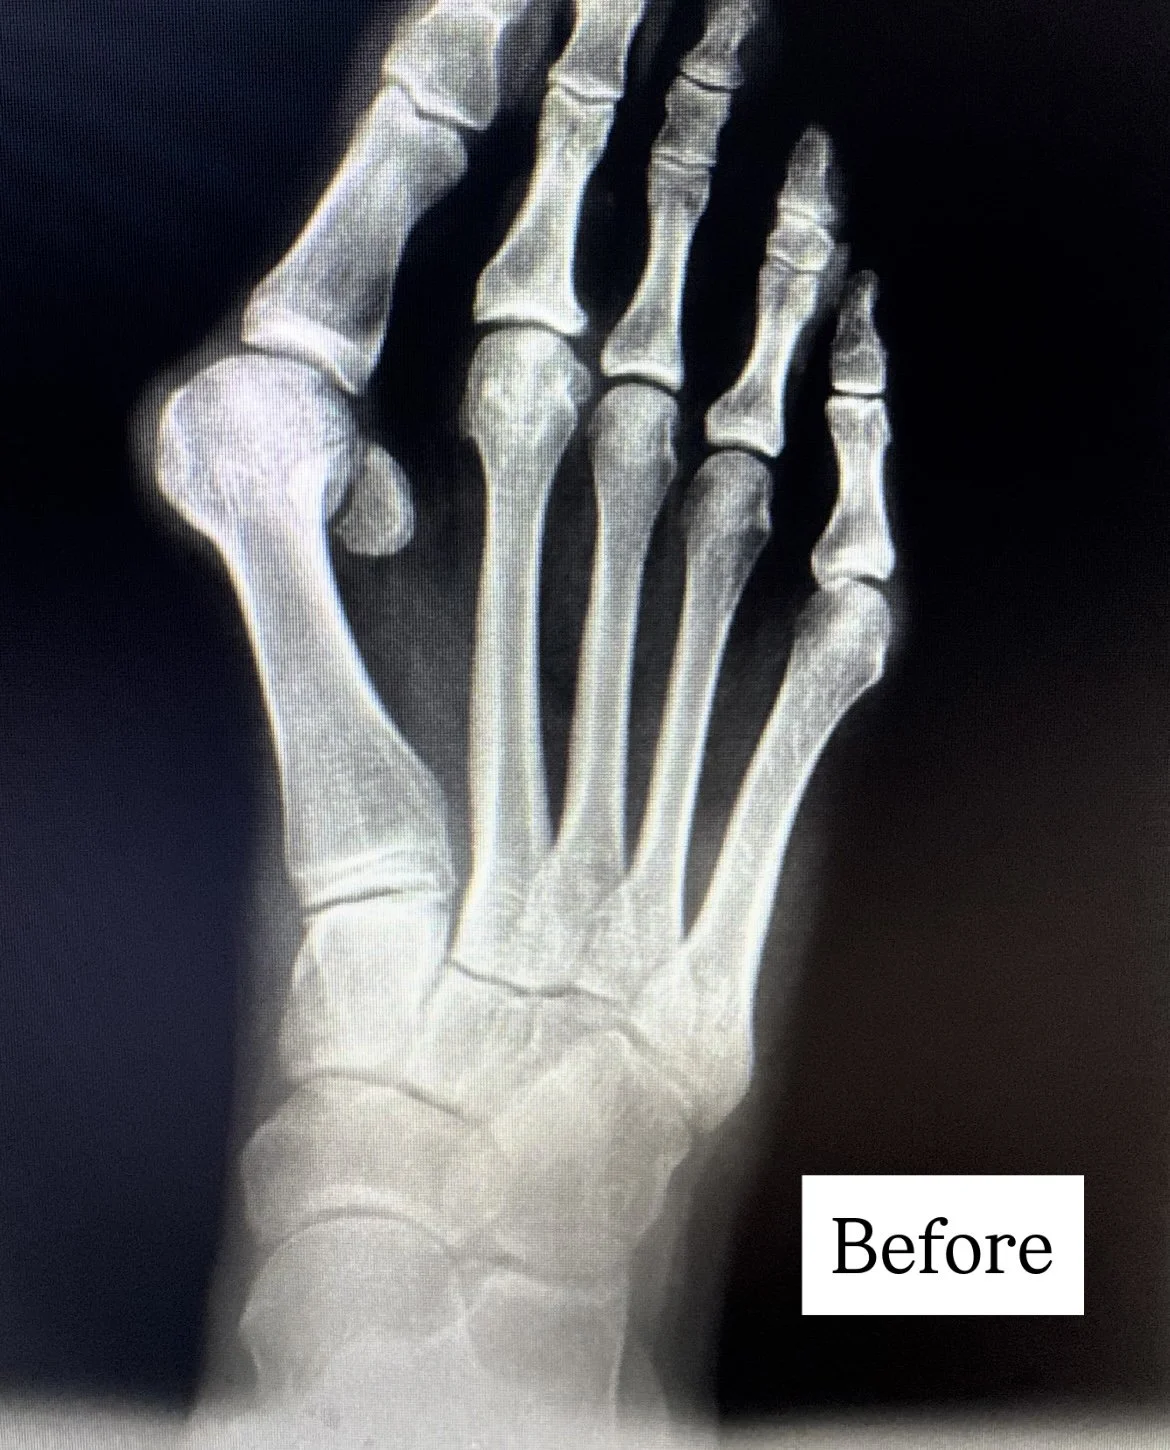

Bunions are more than a bump. A common misconception is that a bunion is simply an overgrowth of bone that can be "shaved off." In reality, a bunion is a complex, 3D deformity caused by an unstable joint in the middle of the foot which allows the metatarsal bone to rotate out of alignment.

Bunions are a 3D problem. While 87% of bunions are 3D problems with abnormal rotation of the metatarsal bone, the majority of bunion surgery is only 2D. When all three dimensions of a bunion are not addressed, there is a 12X likelihood it will recur. That's why Lapiplasty® 3D Bunion Correction was developed; to give patients a better outcome.

Bunions are complex 3D deformities that cause your big toe bones to: unstable foundation Like the Leaning Tower of Pisa, with its unstable foundation, the metatarsal bone starts to lean sideways. The metatarsal bone can elevate up, like a stool with a short leg; transferring excessive load to other toes. The metatarsal bone can rotate, causing abnormal wear and tear on your joints like a car tire out of alignment.